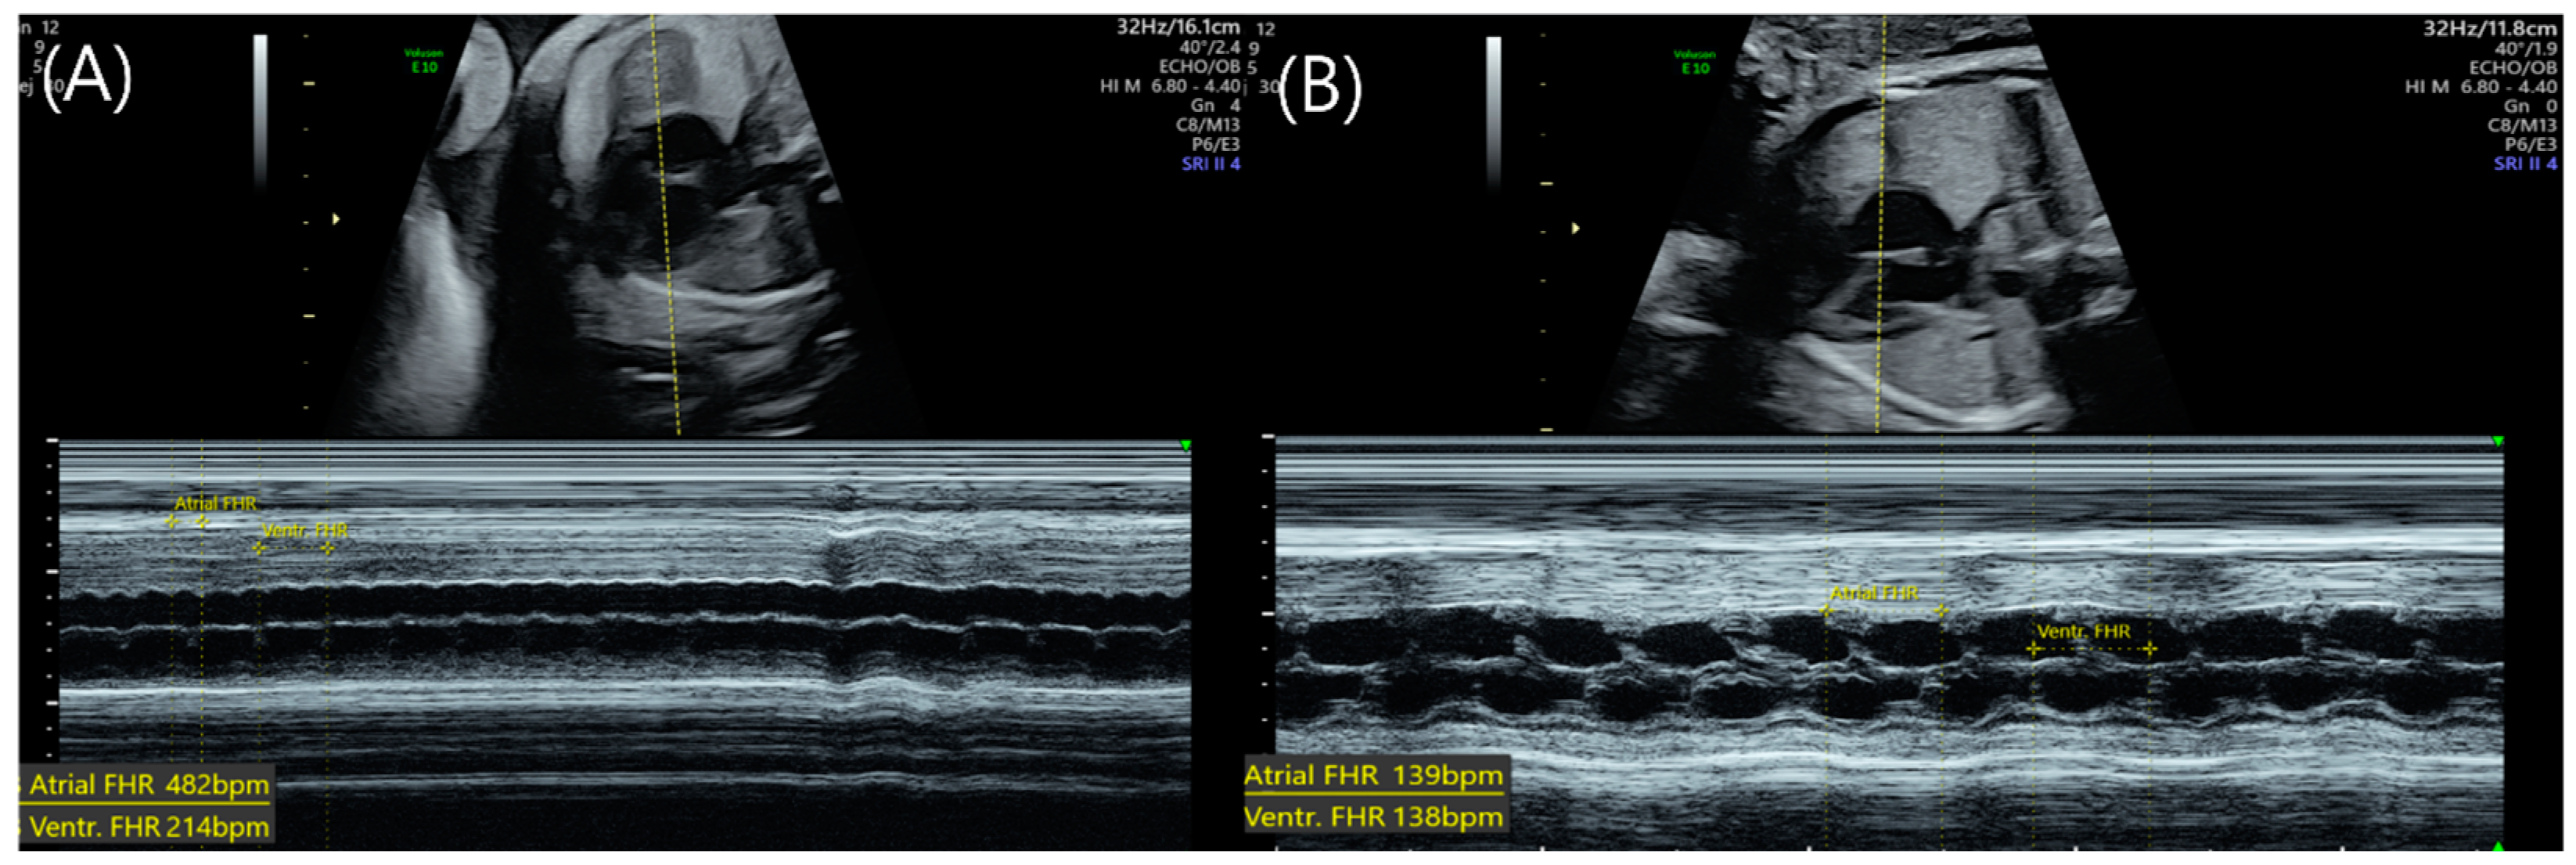

2. Case